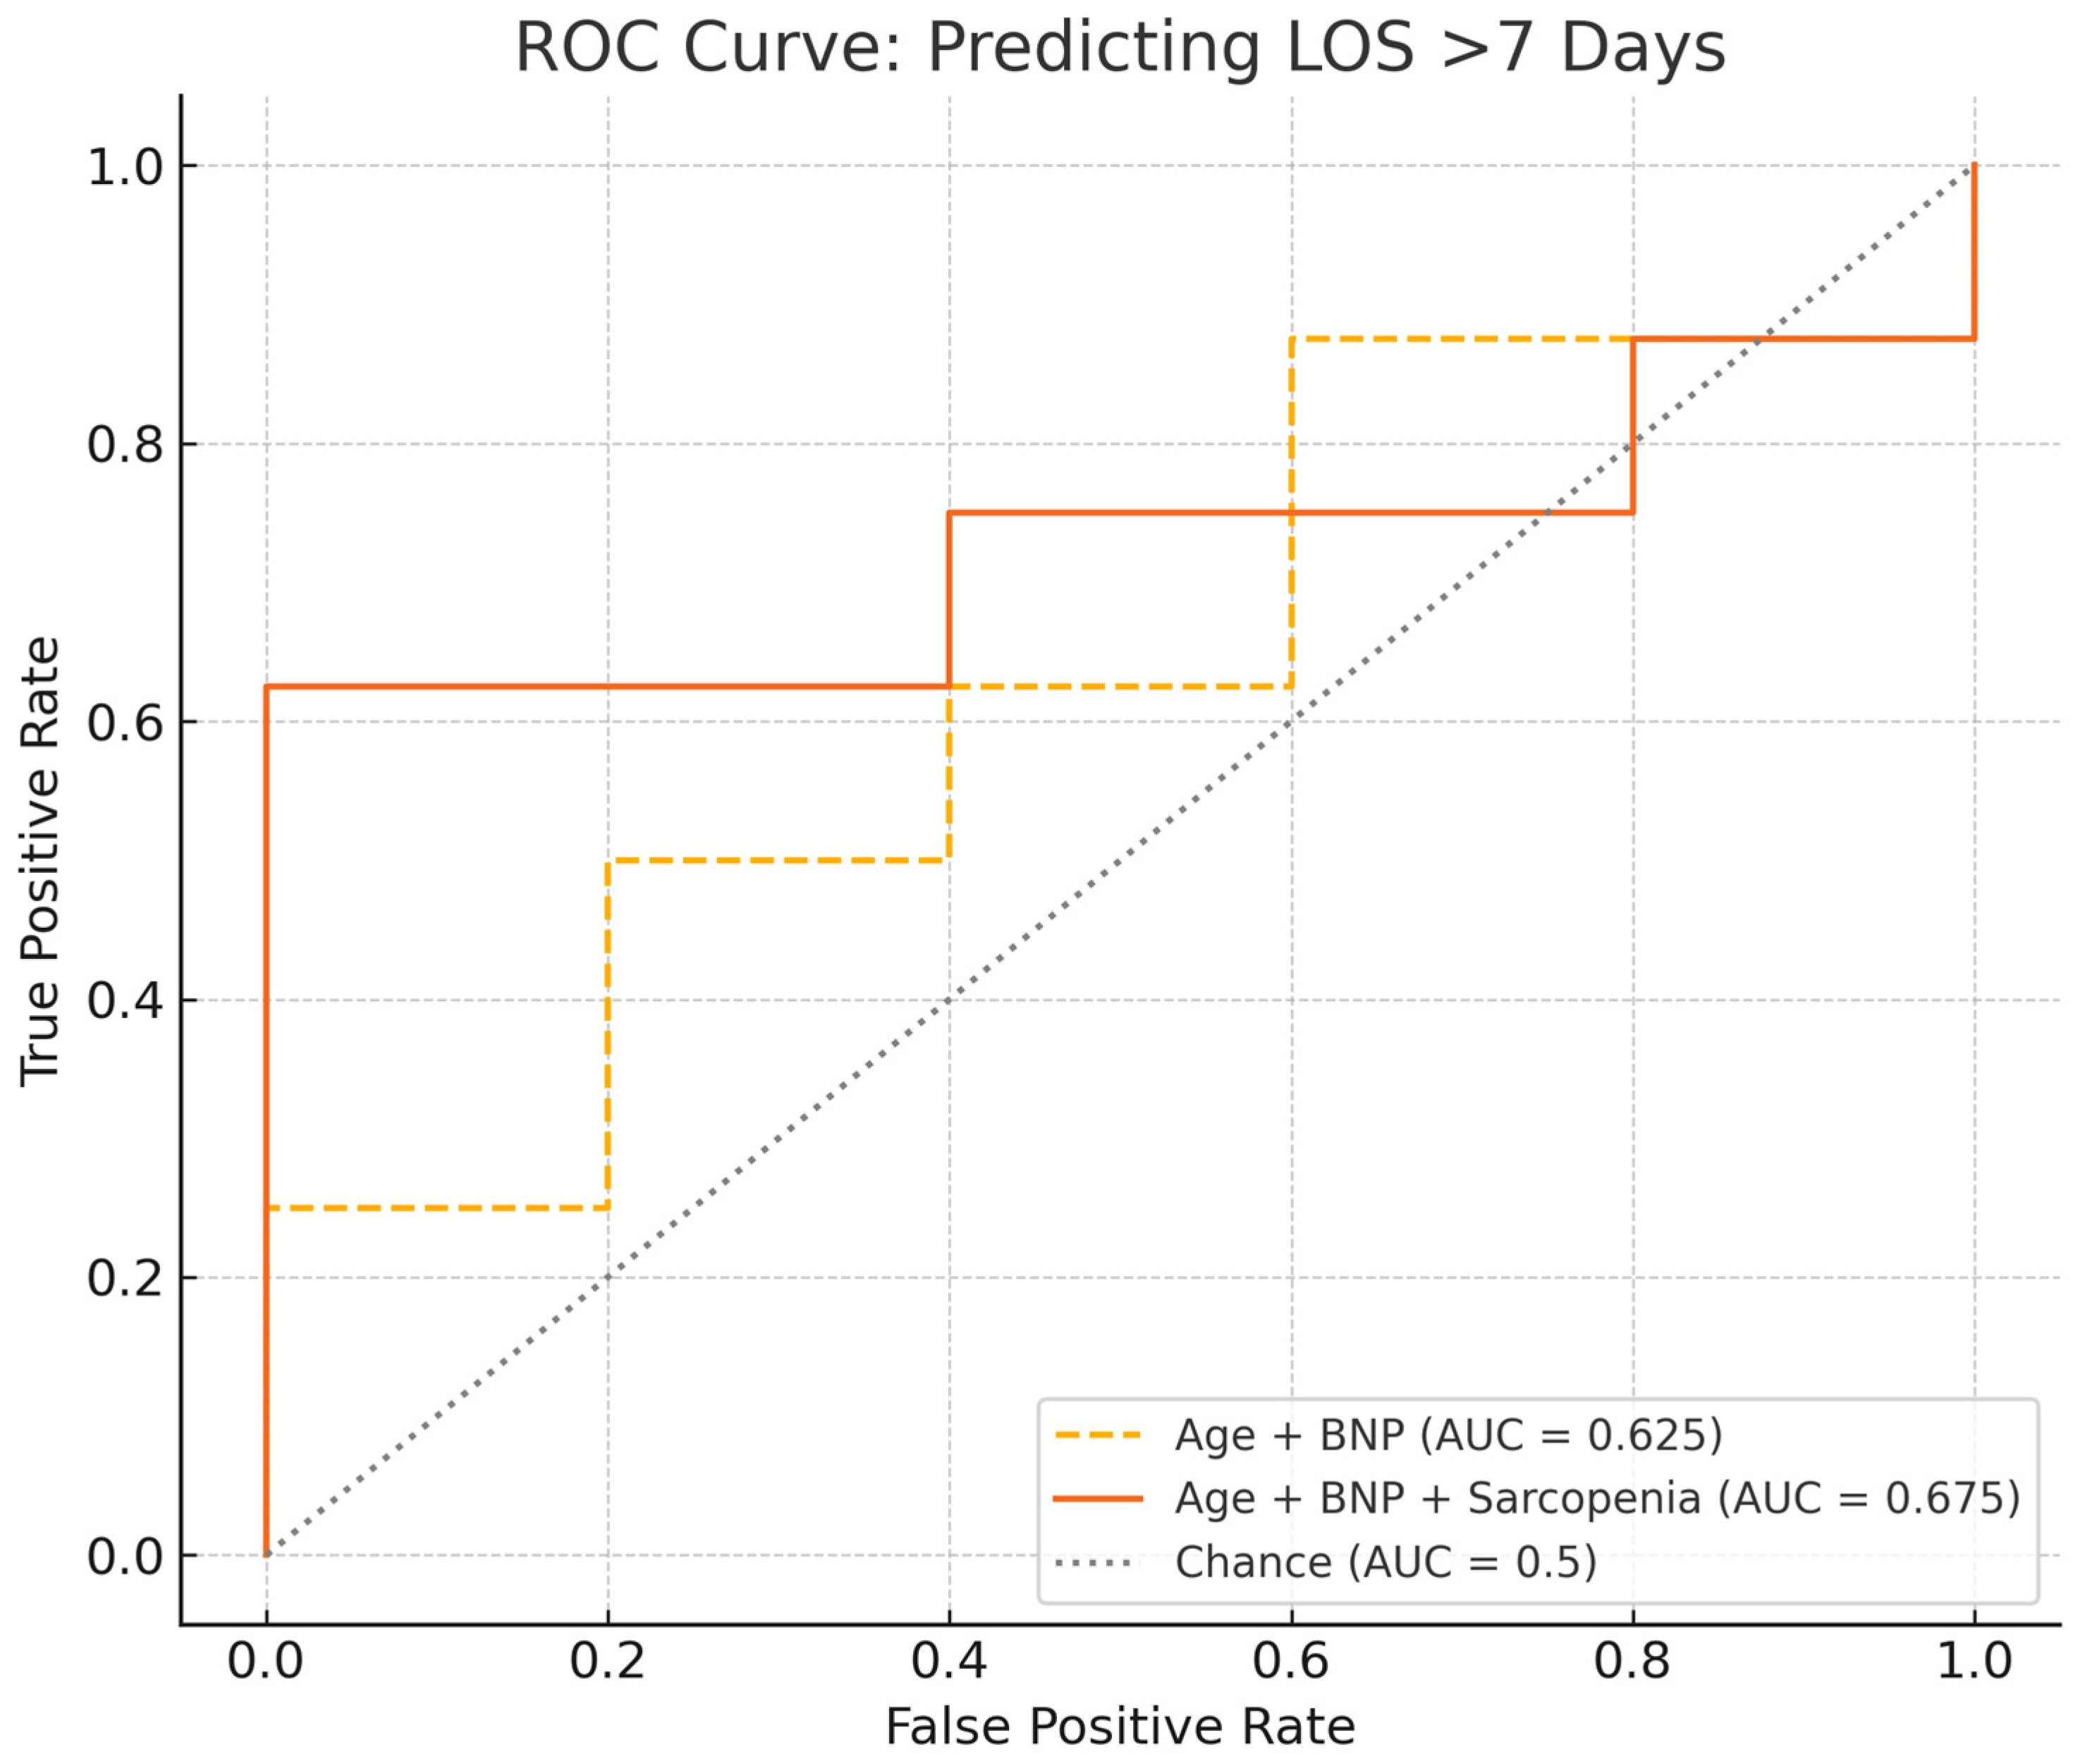

3.3. Clinical Course, Biomarkers, 6MWD, and Post-PTE Specific Outcomes

4. Discussion